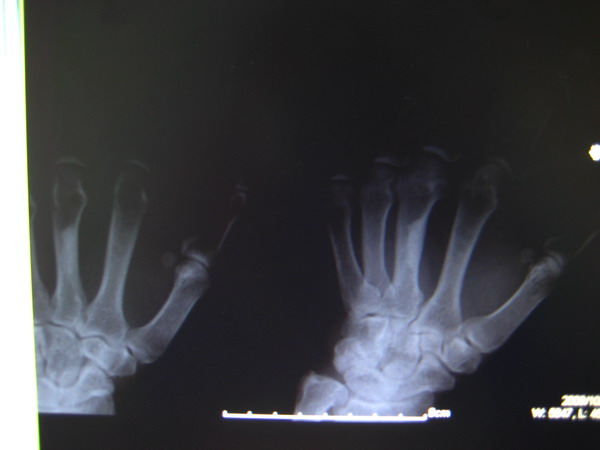

男 53 左手掌指关节肿胀 疼痛

片子太黑,关节看不清。箭头所指为局限性皮质增厚,无意义,多为良性皮质缺损愈后改变。鉴别:蜡泪样骨病、内生骨瘤。

看到了一个局限性的致密影,但是意义不大

支持考虑局限性皮质增厚。

局限性皮质增厚

局限性皮质增厚。

局限性皮质增厚??---请结合临床!!

局限性皮质增厚。鉴别内生软骨瘤

指跖骨的局限性皮质增厚,多考虑为正常变异。